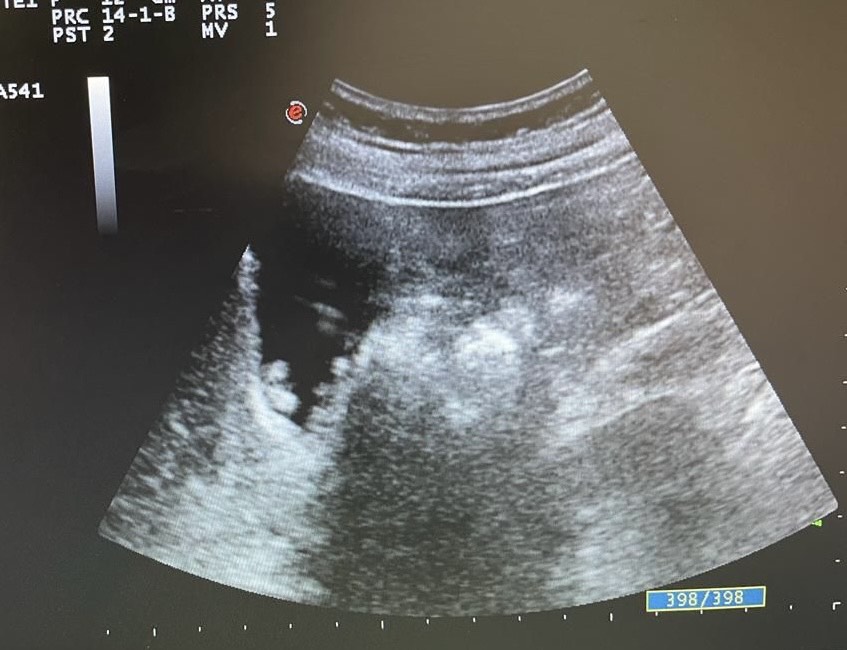

Mentalmente describí las lesiones,  se trata de lesiones múltiples hiperecogénicas  y adheridas a la pared vesicular y que no producen sombra posterior.

Confirmé que no se trataba de colelitiasis sino que en mi opinión eran múltiples pólipos vesiculares y alguno de ellos cercano a 1 cm de diámetro, sin poder descartar malignidad con la ecografía, por lo que solicité un TC abdominal que informó de un único pólipo vesicular de 6 mm.

Desde la consulta de cirugía se solicitó ecografía reglada y control en 6 meses que informó de múltiples engrosamientos nodulares en relación con pólipos (más de 10), los de mayor tamaño alcanzan 9 mm de grosor máximo. Alitiasica.